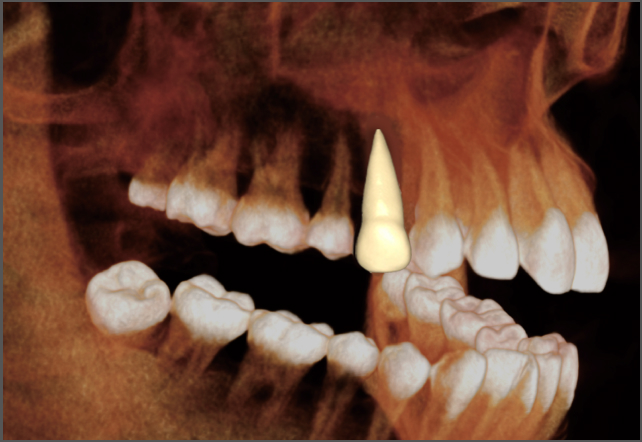

• lamtau 單顆牙齒分割

單顆牙齒分割

• lamtau 模擬種植

模擬種植